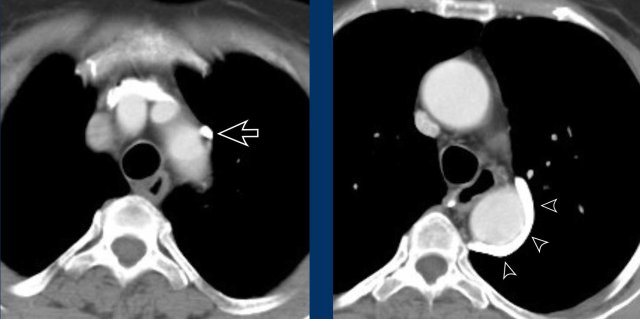

Images

Hypertrophy of the bronchial artery up to 4 mm in diameter (arrows) with a small aneurysm (arrowhead).